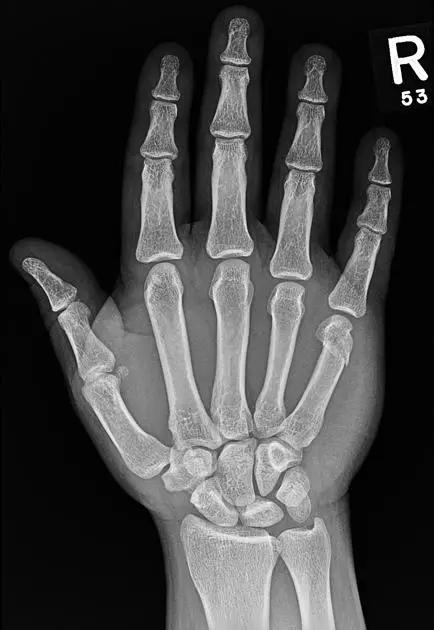

7. Boxer's 骨折

第 5 掌骨颈骨折伴有掌骨头向掌侧移位。